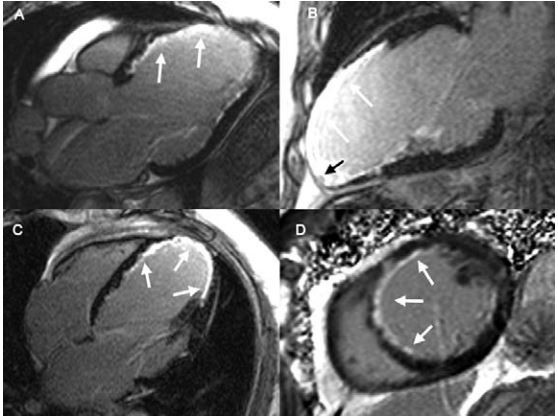

Paciente com 58 anos, hipertenso, diabético e ex-tabagista, transferido de outro serviço para nossa unidade clínica com infarto anterior evoluído com início dos sintomas há mais de 7 dias. Realizou cateterismo cardíaco que evidenciou oclusão proximal da A.DA. Ecocardiograma evidenciou disfunção segmentar acometendo toda parede anterior com afilamento do miocárdio nos segmentos acometidos. A equipe clinica optou por pesquisar viabilidade miocárdica com Ressonância Magnética (RM) Cardíaca, com as imagens representadas a seguir:

É correto afirmar: